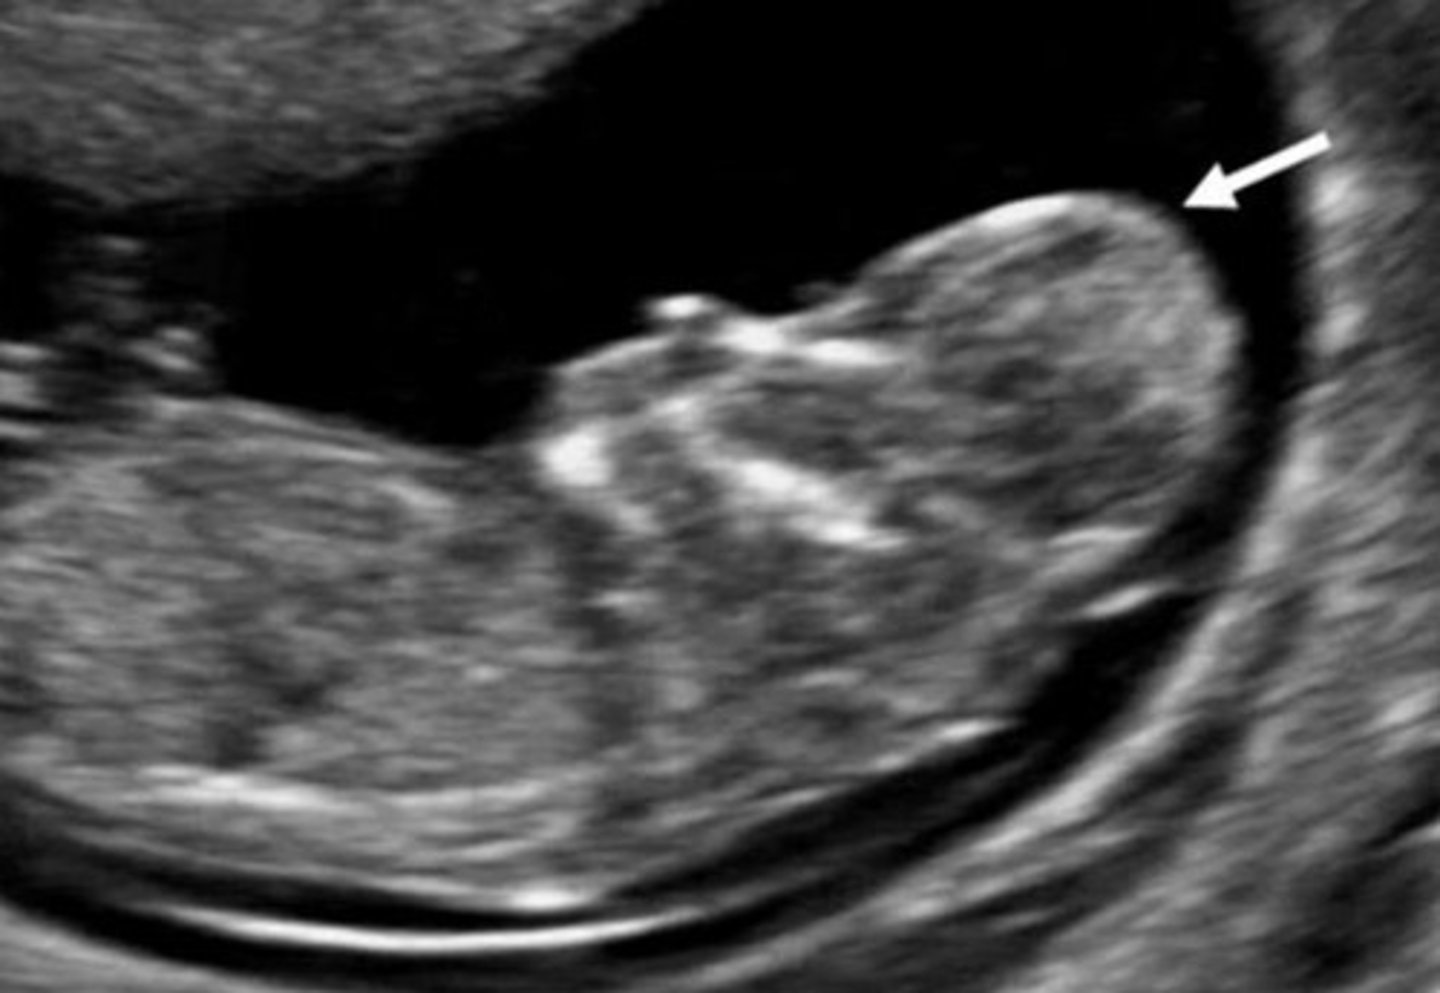

Cloverleaf Sign

Sign of craniosynostosis